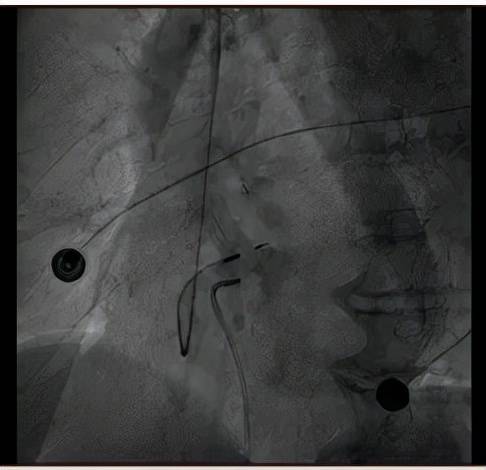

起搏器手术过程中的影像资料

文章图片